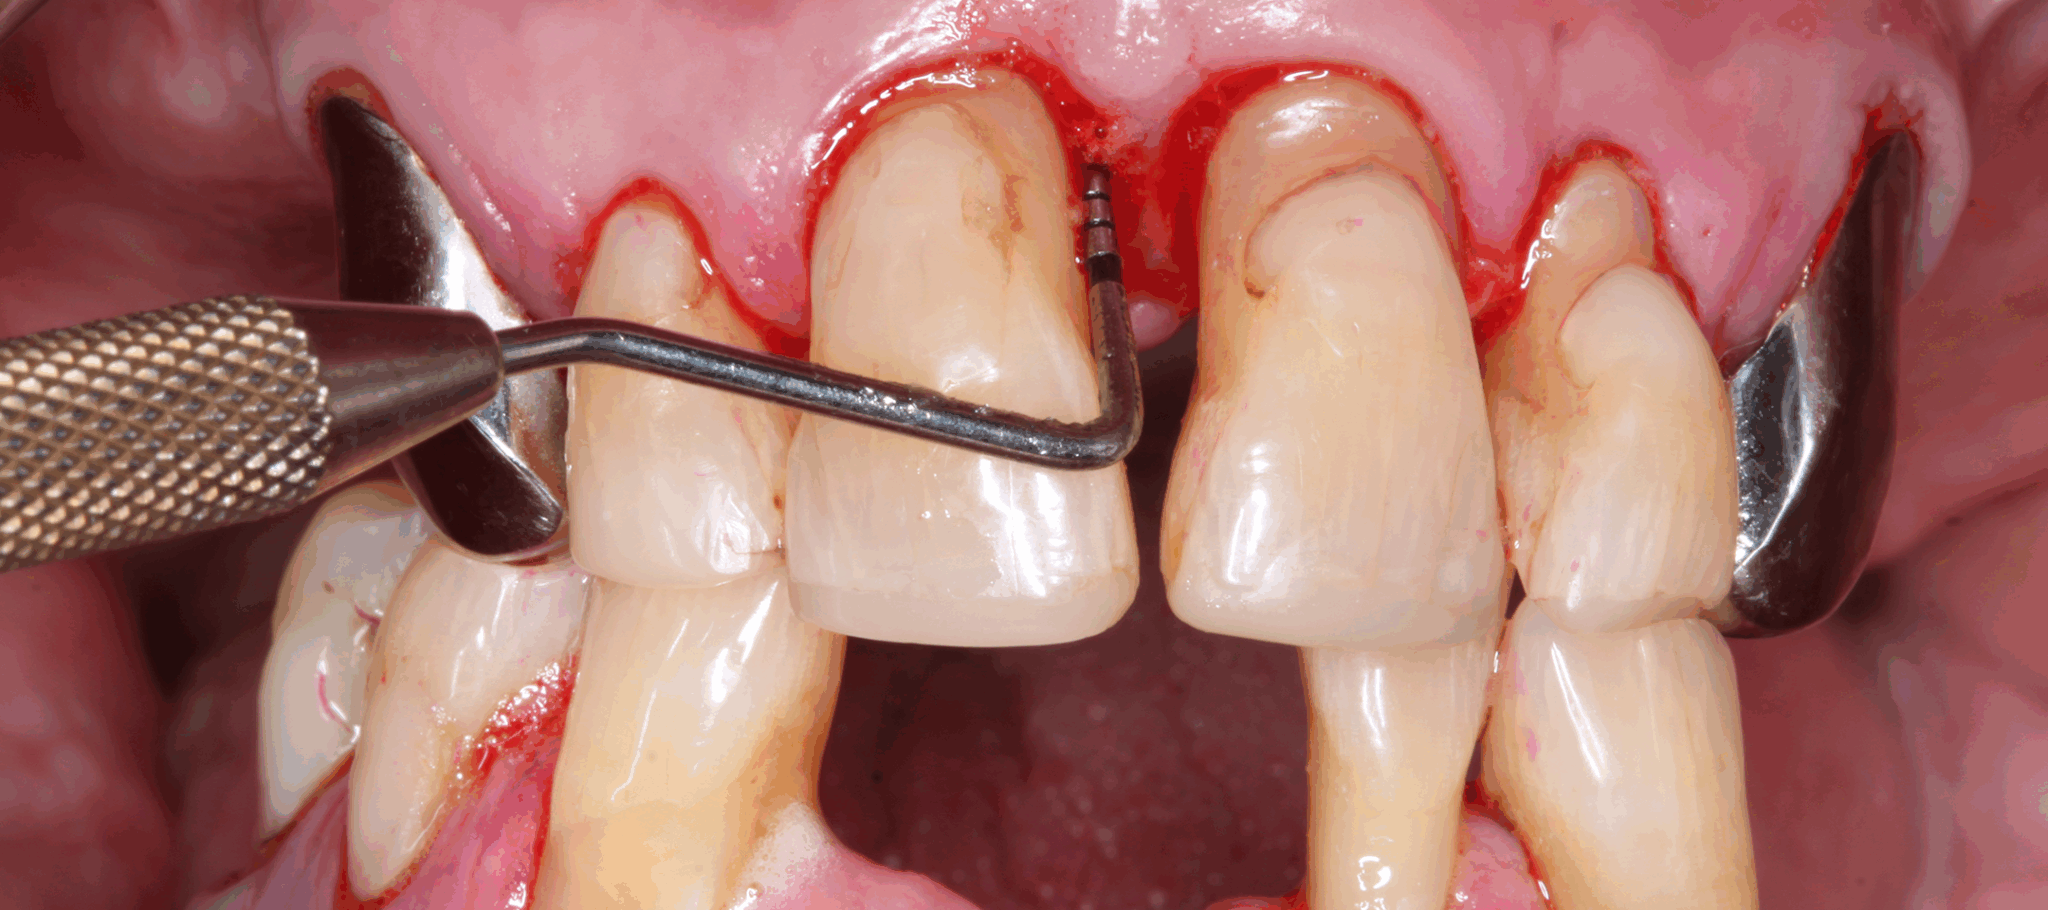

Klinische und radiologische Dokumentation eines 82-jährigen männlichen Patienten (geb. 4.2.1943) mit generalisierter Parodontitis Stadium IV Grad C. Im Vorfeld der systematischen parodontalen Therapie traten nach den Extraktionen der Zähne 31 und 41 orale Blutungen, die zahnärztliche Interventionen im Rahmen von Notfallbehandlungen erforderten, auf.

Foto: Prof. Dr. Clemens Walter